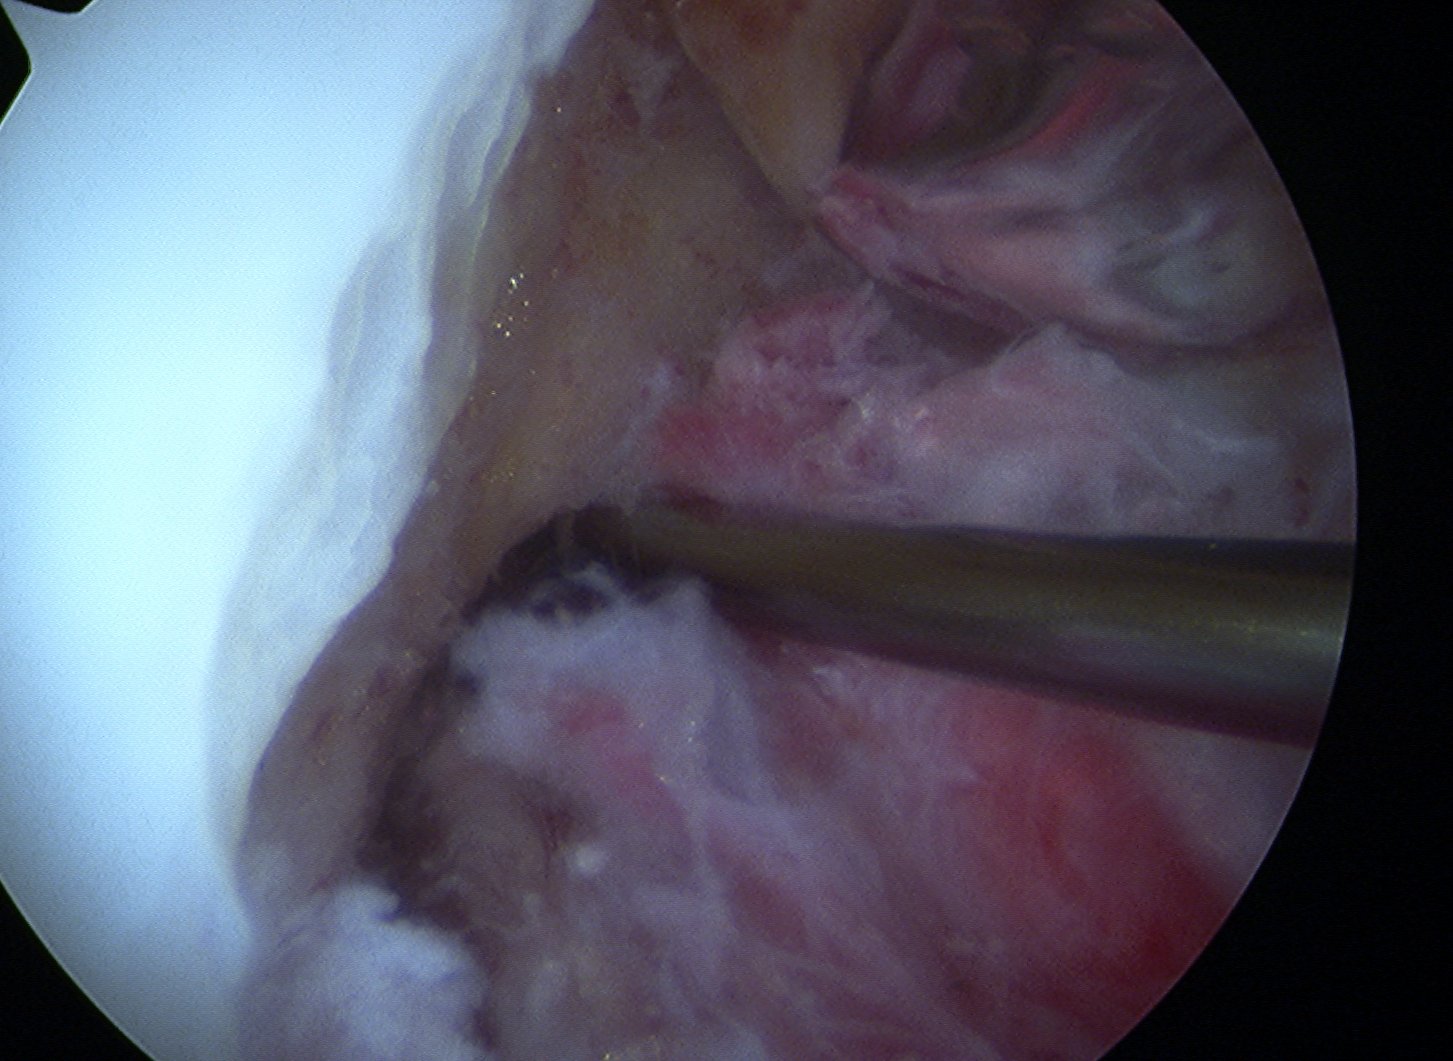

Transtibial femoral tunnel

- need to use 7 mm offset jig to prevent posterior wall blowout

- pass femoral beath pin at 90o

- drill femoral tunnel 10 mm wide

- 5mm deeper than bone graft length

- if bone plug 20 mm long, drill 25 mm

- if bone plug 25 mm long, drill 30 mm

- need to thoroughly clean tunnel of bone debris

- can help to pass acorn reamer twice